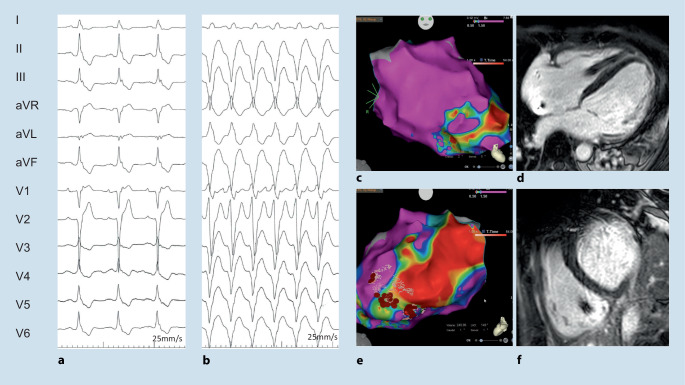

Fig. 3.

A 49-year-old male with biopsy-proven cardiac sarcoidosis. a Atypical right bundle branch block (RBBB) with prominent second component of the QRS complex in the presence of atrioventricular block I. b Sustained hemodynamically tolerated ventricular tachycardia (CL 430 ms). c–f Electro-anatomical CARTO activation map and bipolar right ventricular voltage map with extensive fibrosis that correlated with the cardiac magnetic resonance imaging illustrated by late gadolinium enhancement